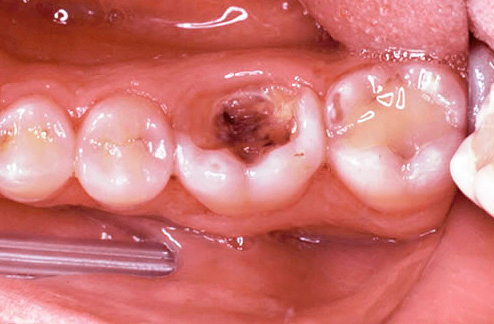

I sintomi della pulpite fibrosa cronica (a volte chiamata semplice cronica) sono dolore da tutti i tipi di irritanti: freddo, caldo, dolce, dall'aria fredda, ecc., Che non scompaiono a lungo dopo aver eliminato il fattore irritante. Inoltre, questa patologia specifica è caratterizzata da un sintomo così specifico come l'insorgenza di dolore prolungato durante il passaggio dal freddo a una stanza calda.

A volte la pulpite fibrosa cronica è asintomatica. Ciò è dovuto alla speciale localizzazione della cavità cariata (ad esempio, sotto la gomma), quando gli stimoli non possono influenzarla, o al messaggio passante della cavità e della camera pulpare - in tali casi non c'è gonfiore e scoppio della polpa e non ci sono dolori, rispettivamente.

L'ispezione visiva del dente con una sonda appuntita e uno specchio fornisce circa il 50% delle informazioni necessarie. In termini di aspetto della cavità, indolenzimento del suo fondo, comunicazione con la camera pulpare (il luogo in cui si trova il "nervo"), si può già ipotizzare la pulite cronica.

Se c'è un messaggio con una cavità cariata e compaiono dolore e sanguinamento quando si sondano con una sonda acuta, allora con un alto grado di probabilità è cronico pulite fibrosa. Con un cambiamento nel colore dei denti, l'aspetto di un'ombra grigia, con una grande quantità di tessuto cariato ammorbidito nella cavità del dente, quando il "nervo" viene parzialmente distrutto e il dolore si verifica solo quando si sondano i canali, allora è molto probabilmente una polpite cranica cronica. La comparsa di tessuto troppo cresciuto all'interno della cavità in combinazione con l'indolenzimento quando lo sondano il più delle volte indica una polpite ipertrofica cronica.